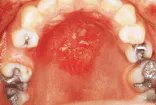

Drug-related allergic mucosal reaction

The problem: Intraoral examination revealed a large, diffuse lesion. The lesion appeared to be erosive and ulcerated.